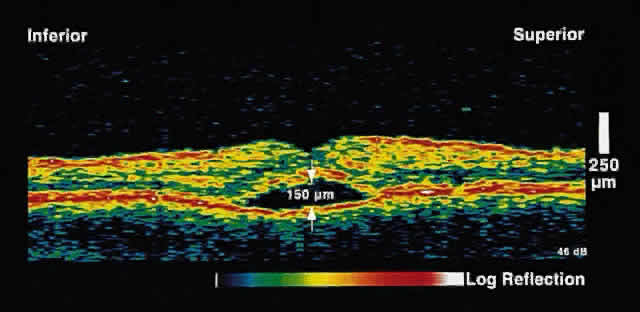

choriocapillaris/RPE layer.  Fig. 2. OCT image shows a neurosensory detachment secondary to central serous chorioretinopathy. The

difference in optical reflectivity between the posterior

boundary of the neurosensory retina and the underlying serous

fluid allows even small areas of elevation to be detected. Fig. 2. OCT image shows a neurosensory detachment secondary to central serous chorioretinopathy. The

difference in optical reflectivity between the posterior

boundary of the neurosensory retina and the underlying serous

fluid allows even small areas of elevation to be detected.